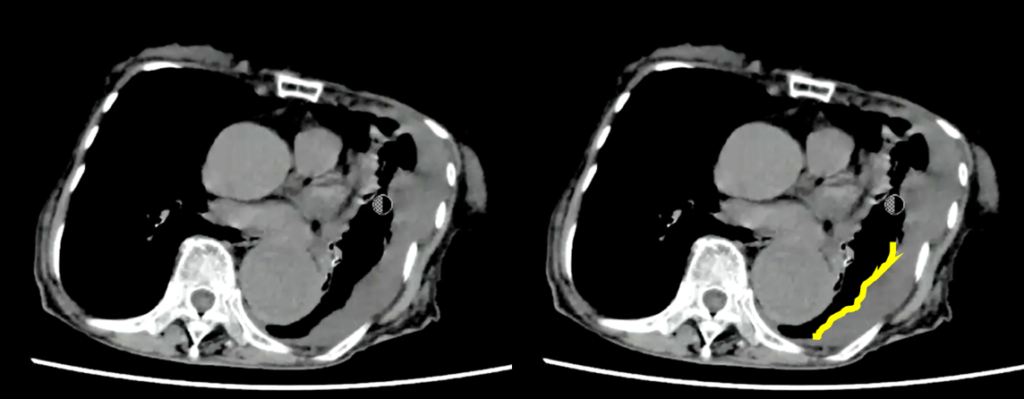

胸部大動脈の著明な拡張と、その周囲に高吸収域を認める(大動脈破裂、contained ruptureを示唆)。

大動脈が大きいのと周囲に高吸収域を認めます。high attenuating crescent signと言われるもので、

これを見た時には大動脈の破裂を疑うべきです。やっぱり寝台から下ろすのはちょっと良くないかなと思います。

大動脈というのは基本的に横断面では丸いものなので、この辺縁を追っかけていくと一部が突出っていうのは異常な突出なので、ここはもう出血・血種がここにできているんじゃないかなっというのは想像できると思います。

あと、胸水も普通の胸水とは違って凹凸状に、肺を押すような感じで、CT値も若干高いことから血性胸水なの かもしれないというのを推測することができます。

この症例はimpending ruptureではないんですよね 。もうすでに破れてるcontained ruptureに一致します。破れてるんだけど肺が押してるという状況です。もうすでに破れそう切迫破裂じゃなくてすでに破れてるという状況なので 、そういうのも合わせて手術適用ないという判断がされたと考えます。